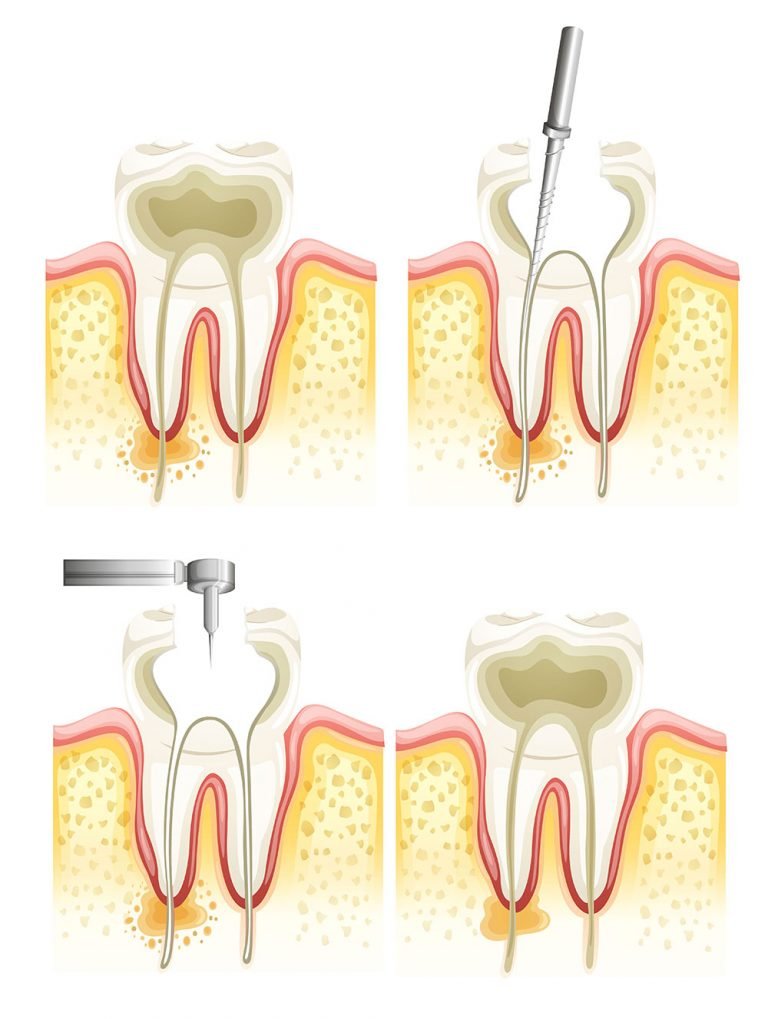

Root canal therapy is needed when the nerve of a tooth, also known as the pulp, is affected by decay or infection. The idea of the therapy is to keep the natural tooth and to recover its normal functions. Usually, root canal treatment is needed when there is pulpitis – complicated caries that reached the pulp. Another case when root treatment is needed is inflammation around the roots of the tooth, resulting in changes in tissues in the form of granulations.

The treatment has some phases. In order to save the tooth, the pulp (the living tissue inside the tooth), nerves, bacteria, and any decay are removed and the resulting space is filled with special, medicated, dental materials, which restore the tooth to its full function.

The physicians in dental clinic Estetica use modern and effective methods for treatment of pulpitis and periodontium by mechanically shaping of the root canals, which makes easier the 3D filling with warm condensation. Root canal treatment is highly successful and usually lasts a lifetime, although on occasion, a tooth will have to be retreated due to new infections. By placing a tooth filling the missing part of the crown is recovered.

Retreatment of the tooth may be necessary if the first treatment is unsuccessful. Although the sequence is the same as in the initial treatment, it requires much more attention when removing the root canal filling or finding a new one. When a retreatment occurred, the tooth must be opened again, used filling materials from the first treatment – removed and to make a careful examination of the tooth for additional canals or a new infection. Once cleaned and shaped, the canals are filled again.